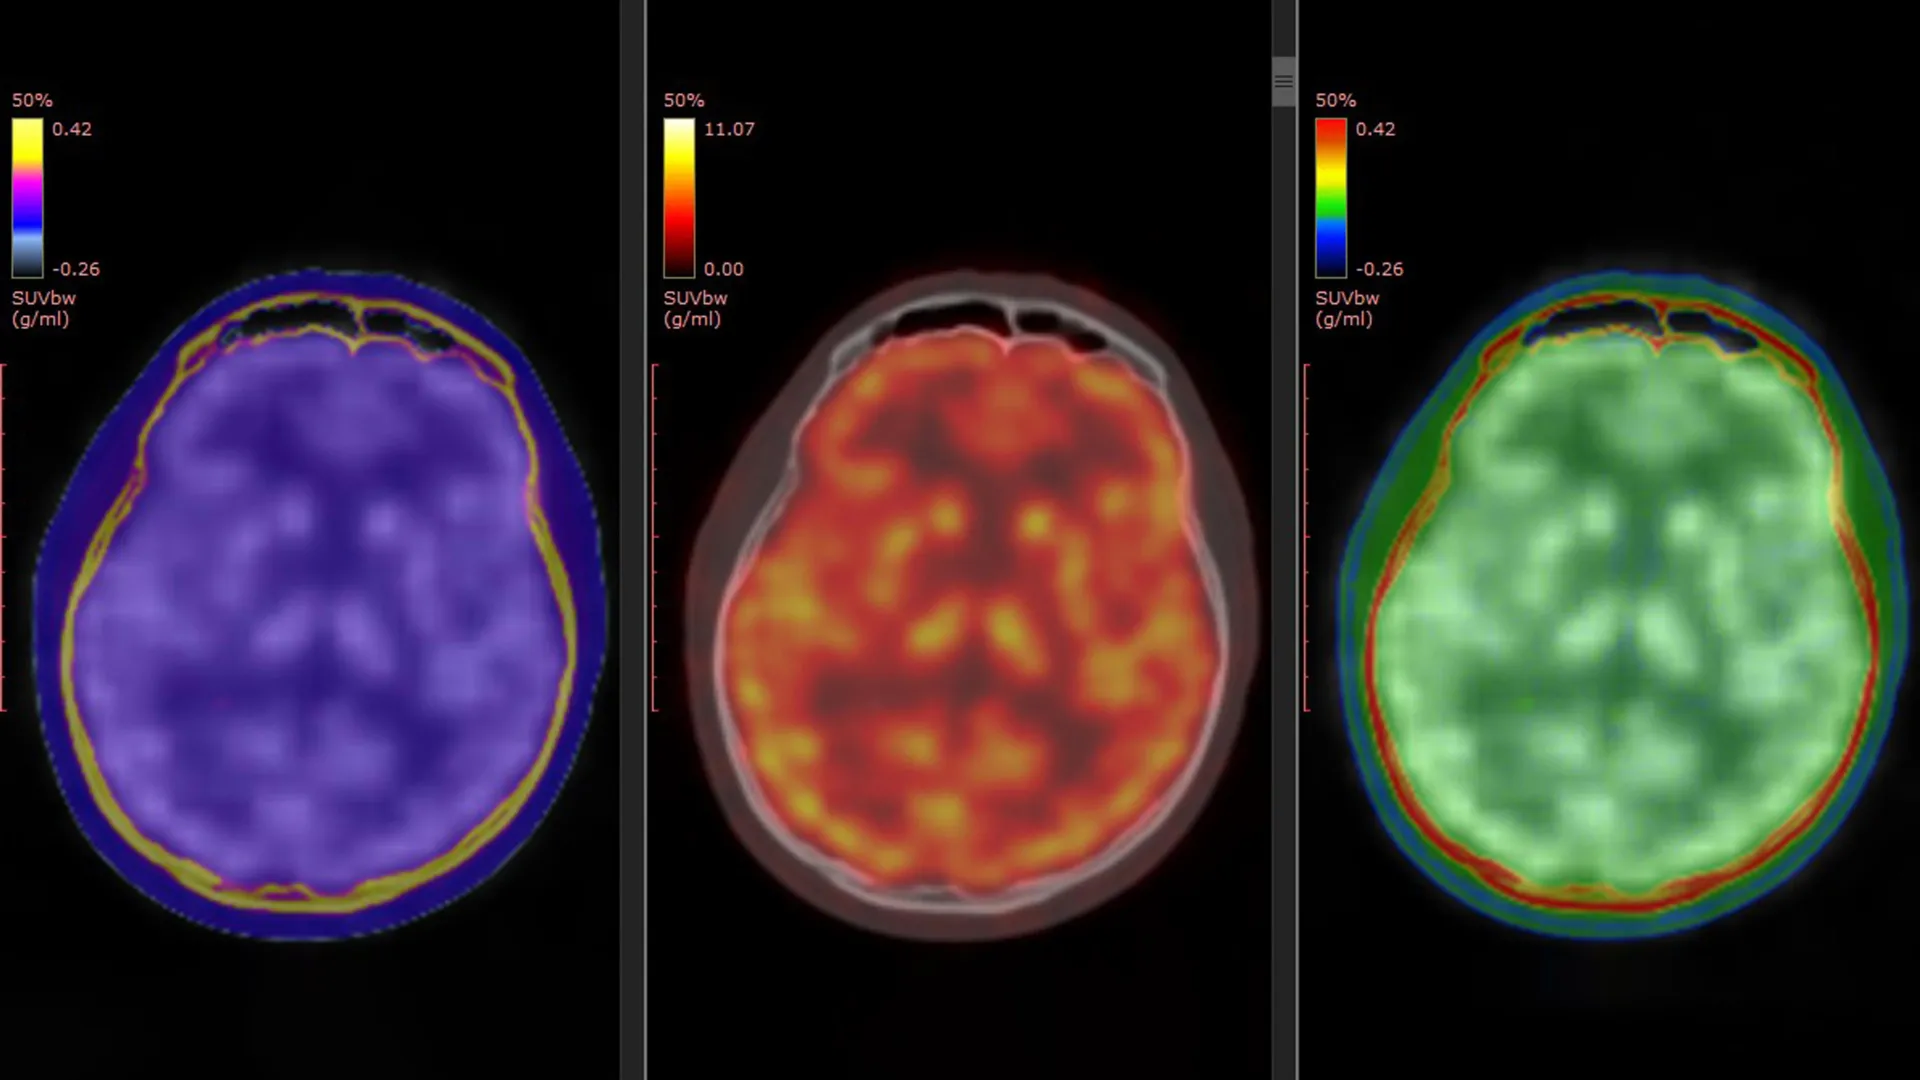

The cornerstone of this pivotal research was a novel PET tracer, designated as [11C]K-2, previously developed by Professor Takahashi’s group. This sophisticated tracer possesses the unique capability to visualize cell-surface AMPARs directly within the living human brain. Prior to this study, laboratory experiments and animal models had strongly suggested a link between ketamine’s antidepressant effects and AMPAR activity. However, the present investigation marks the first time this critical process has been directly evidenced in human subjects.

Participants in the TRD group were administered either intravenous ketamine or a placebo over a two-week treatment period. To capture the dynamic changes occurring in the brain, PET brain imaging was performed at two key junctures: immediately preceding the commencement of treatment and again following the final ketamine or placebo infusion. This meticulous timing allowed researchers to directly compare alterations in AMPAR levels and their distribution across the brain before and after intervention.

Furthermore, the administration of ketamine did not elicit uniform changes in AMPARs across the entire brain. Instead, the research demonstrated a sophisticated interplay between improvements in depressive symptoms and dynamic, region-specific adjustments in AMPAR levels. In certain cortical areas, an increase in AMPAR density was observed, potentially signifying enhanced neuronal connectivity and communication. Conversely, a reduction in receptor density was noted in regions critically involved in reward processing, particularly the habenula. The habenula, often referred to as the "anti-reward center," plays a significant role in processing negative emotional states, and its modulation by ketamine is a key area of interest.

"Ketamine’s antidepressant effect in patients with TRD is mediated by dynamic changes in AMPAR in the living human brain," Professor Takahashi elaborated. "Using a novel PET tracer, [11C]K-2, we were able to visualize how ketamine alters AMPAR distribution across specific brain regions and how these changes correlate with improvements in depressive symptoms."